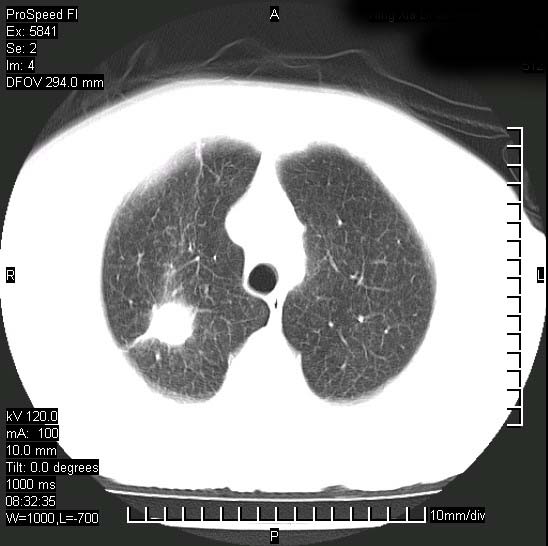

胸痛,咳嗽,气短一周,无发热。右上肺见一结节灶,边缘刺角,内见多个小钙化结节。考虑结核球?肿瘤? 余无异常没有上传。

支持结核球诊断但建议薄扫

胸膜是受侵的,考虑感染,结核球可能性大

考虑结核球,并胸膜局限性增厚!!